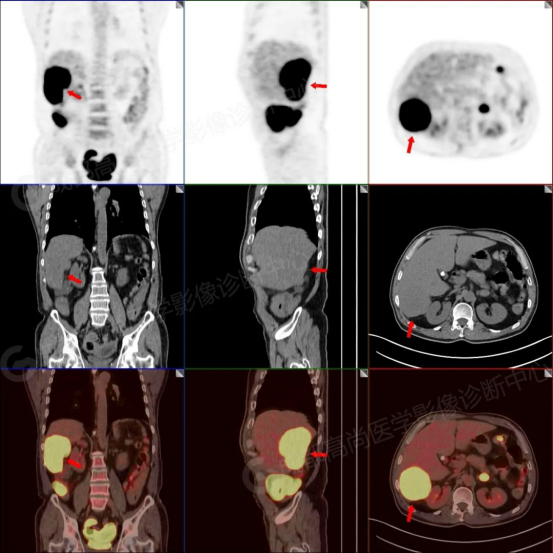

D7:PET-CT显示腹膜转移灶全部失活